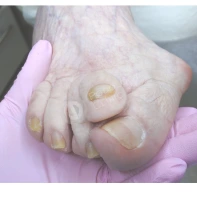

Грибковые поражения ногтей, приводящие к утолщению и огрублению ногтевой пластины, также способствуют ее врастанию в околоногтевой валик пальцев.

- При второй ноготь уплотняется, приобретает тусклый цвет. В месте, где происходит травматизация мягких тканей пальца, возникает небольшая язвочка, при надавливании на которую может выделяться гной.

- При третьей стадии ногтевая пластина становится тонкой и ломкой. Околоногтевой валик увеличивается в размерах, в области вросшего ногтя разрастается грануляционная ткань — богатая сосудами и новыми клетками молодая соединительная ткань зернистой структуры.

Позволяет удалить с помощью скальпеля часть или всю ногтевую пластину вместе с патологически измененными тканями. Это проверенная временем техника, которая в ряде случаев предпочтительнее более современных методов. Ее используют, когда воспалительный процесс запущен, присутствует выраженное гнойное отделяемое или грануляционная ткань в значительных объемах. Если ноготь сильно деформирован, например вследствие онихомикоза, хирургическое иссечение может стать единственным способом полностью удалить измененные ткани. Этот метод также выбирают, если необходима пластика ростковой зоны, чтобы предотвратить повторное врастание.